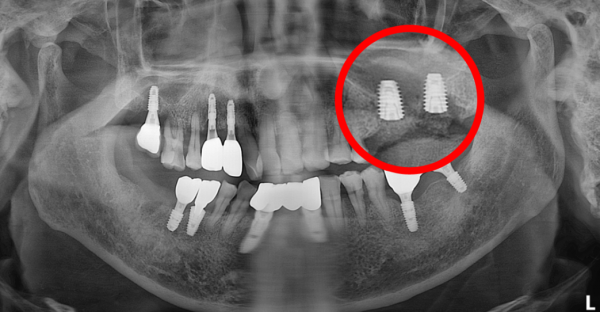

5) 수술 후 영상 평가

수술 직후 파노라마에서 확인한 내용은 다음과 같습니다.

* 상악동 거상된 공간의 형태가 비교적 안정적으로 유지됨

* 골이식재의 분포가 한쪽으로 치우치지 않도록 관리됨

* 임플란트 위치와 방향이 계획 범위에서 확인됨

현재는 치유 과정을 거치며 추적 관찰 중이며, 일정 기간 후 2차 수술 및 보철 단계로 넘어갈 예정입니다.